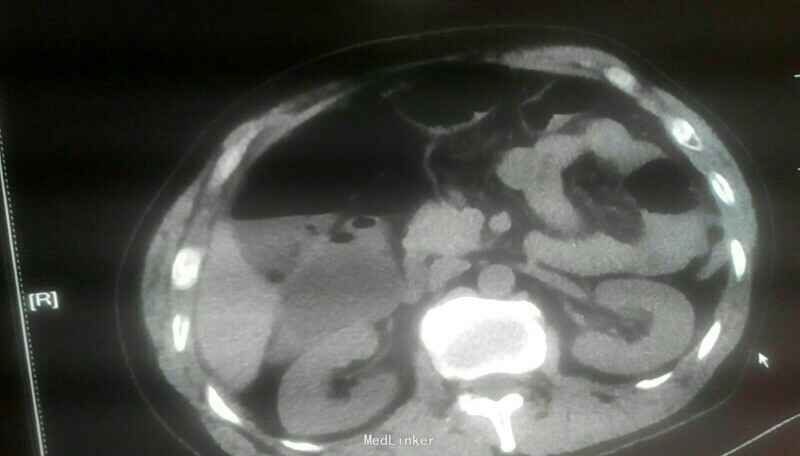

辅助检查:血常规,白细胞:4.99×109/L,中性粒细胞,4.23×109/L;血糖10.57mmol/L;白蛋白33.9g/L;腹部CT:右下腹髂窝渗出并局部肠管扩张积液、考虑阑尾炎可能性大,病理:(阑尾)急性化脓性阑尾炎伴周围炎,部分坏疽;

诊断:急性阑尾炎、急性化脓性腹膜炎、肠梗阻